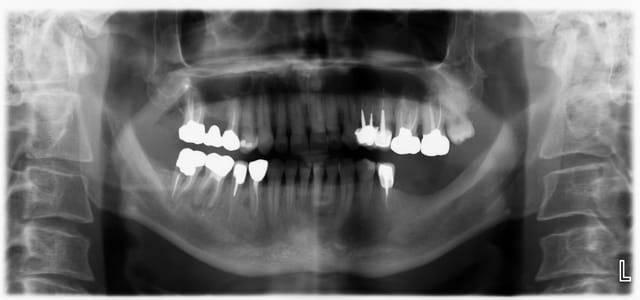

petit cas, commencé il y a quelques années.

C'est de l'ortho mais je suis omnipraticien.

Le cas ou j'ai le plus galéré ( classe 3 et surtout 43 incluse ), mais qui m'apporte beaucoup de satisfaction.

fille d'un ami en plus!